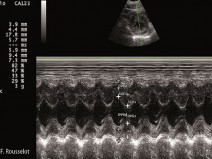

• Echocardiographie niveau débutant

Etre capable de

•  reconnaître les differentes coupes échocardiographiques

•  nommer les différentes coupes

•  reconnaître et nommer les cavités, parois et valves des coupes susnommées

•  réaliser les principales coupes parasternales droites

•  réaliser des tirs en mode Temps Mouvement.